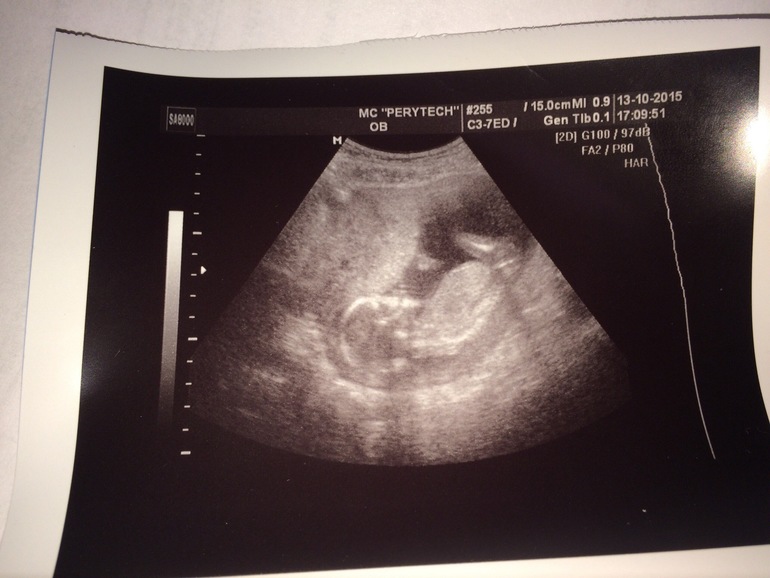

Узи) нам 15,1 )))

наконецто я увидела своего малыша) предположительно сказали девочка) ну посмотрим) муж был рядом смотрел все на одном дыхании) очень счастливые, классно когда говорят что все хорошо)